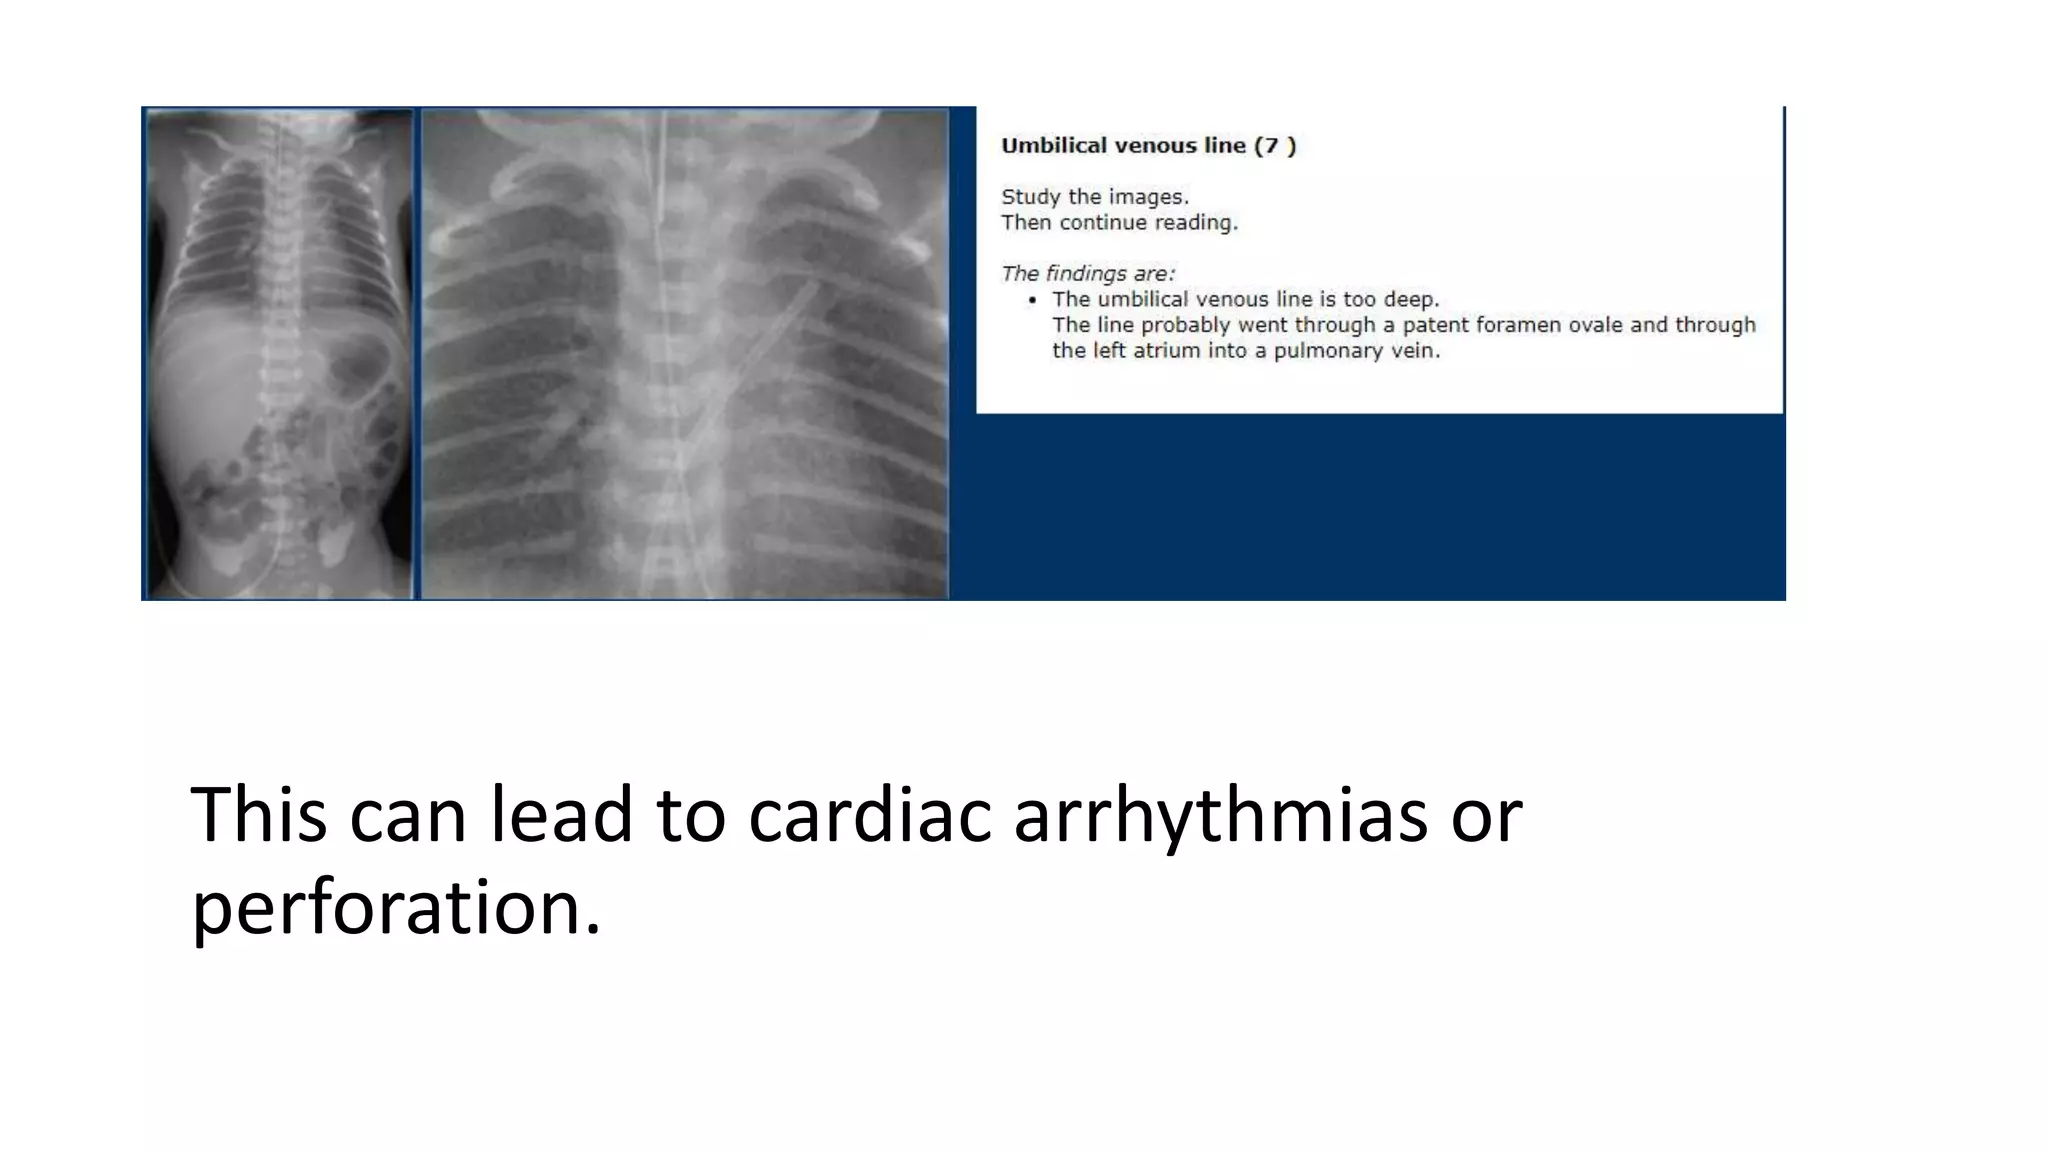

This document provides an overview of neonatal chest x-rays, including when they should and should not be performed, what a normal x-ray looks like, common positions of tubes and catheters, and common causes of respiratory distress in neonates. It discusses the appearance of a normal chest x-ray as well as conditions like respiratory distress syndrome, transient tachypnea of the newborn, meconium aspiration syndrome, and pneumonia. Surgical conditions like diaphragmatic hernia and esophageal atresia are also reviewed.